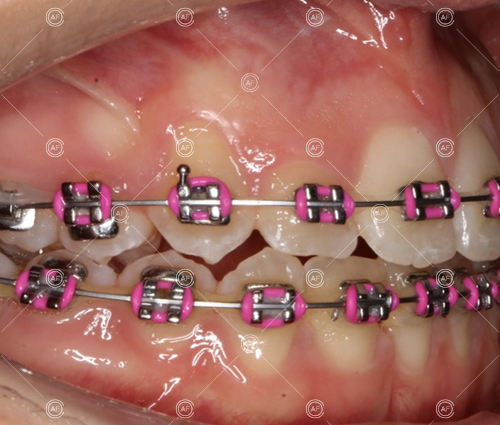

Treatment progressed by starting with thin, flexible nickel titanium archwires of a round diameter, transitioning to a rectangular nickel titanium archwire before eventually working up to a working archwire (1925 stainless steel).

Residual space from the extractions were closed using upper and lower nickel titanium closing coils. Class 2 elastics were used to facilitate space closure in order to gain class 1 buccal segments.